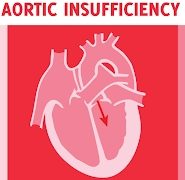

犬の心臓弁膜の疾患(acquired heart diseases)家畜の後天性心疾患については、各種動物でかなりの発生をみていますが、ここではその主なものについて記載します。犬の心臓弁膜の疾患(valvular heart disease...